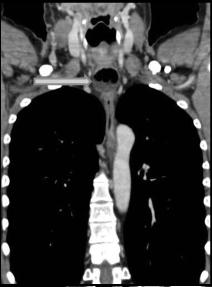

chaussette . Image TDM en fenetre parenchymateuse pulmonaire

,se donne des images si net de oesophage en coupe axiale ,

sagitale et de frontale ( voie image )

Mega oesophage : image radiologique

TDM fenetre parenchymateuse en coupe axiale |

Image Achalasia de oesophage en

coupe TDM sagitale |

Meme cas en coupe TDM frontale ( coronale

) . |